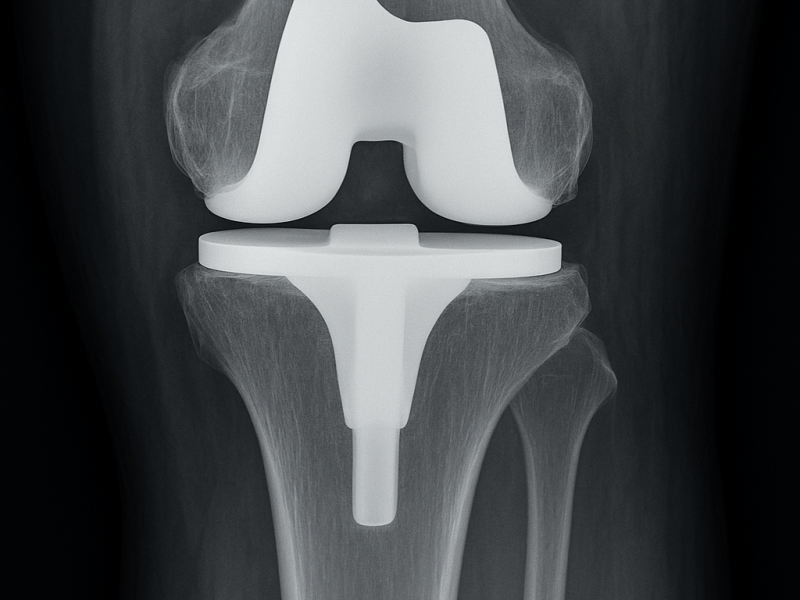

We offer advanced knee replacement surgery using cutting-edge techniques and personalized implants to restore joint function and relieve chronic pain.